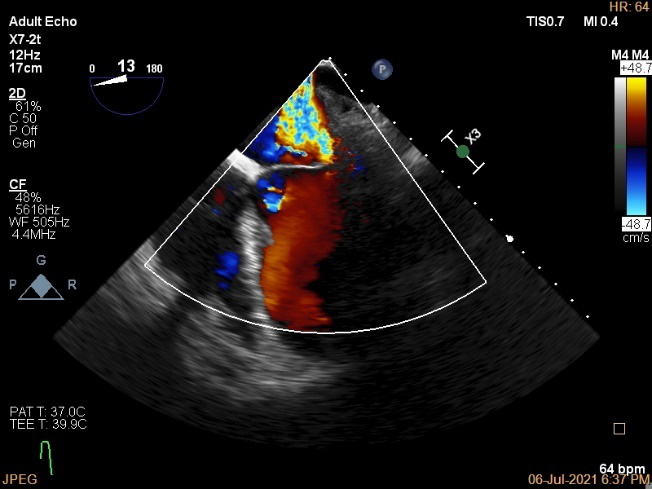

术前超声诊断:

长轴:左室下后壁节异,LAV:101ml,LVEDV:239ml

Bicom:MR(重度),返流束宽15.8mm,返流面积10.6cm²

PISA法定量EROA:0.69cm²,Rvol:168ml,RF:55%

肺静脉血流频谱呈收缩期反向

TEE Bicom返流量评估

TEE 4-Ch view返流量评估